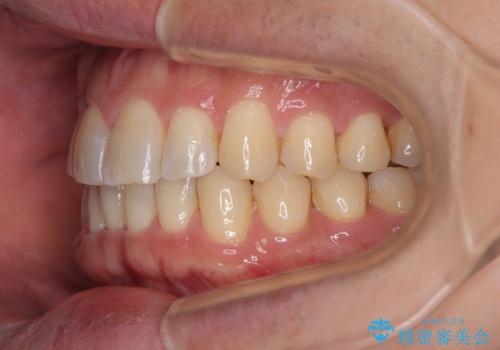

- 上下前歯のデコボコを気にして来院された患者様です。

ワイヤー矯正でもマウスピース矯正でも可能でしたが、短期間で、自身の手を煩わせることなく治療を行いたいとのことで、ワイヤー装置にて矯正治療を行うこととしました。

上顎前歯の舌側転位が顕著であったため、治療期間が長くなると思われましたが、僅か1年で無事に終えることができました。